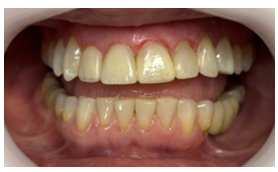

Após a conclusão do tratamento restaurador, o paciente foi acompanhado em consultas de retorno, nas quais foram avaliadas a adaptação gengival, a cor e o contorno das restaurações, bem como sua integridade marginal e a manutenção da higiene bucal. Além desses aspectos técnicos, também foram coletadas informações sobre o conforto pós-operatório e o grau de satisfação estética do paciente em relação ao resultado final alcançado.

Figura 11: Imagem final.

A substituição das facetas foi conduzida com base em protocolos restauradores conservadores, respeitando o espaço biológico e a anatomia natural do paciente. Após a remoção cuidadosa das antigas restaurações, foi realizada a confecção de novas facetas diretas em resina composta, com camadas que reproduziram translucidez natural do esmalte. Durante os retornos clínicos subsequentes, foi constatada uma expressiva melhora nos parâmetros periodontais, com redução significativa da inflamação gengival e ausência de sangramento à sondagem. A adaptação marginal e a morfologia cervical obtidas favoreceram a auto-higienização e restabeleceram a harmonia entre estética e função, confirmando os achados de Peumans et al. (2018) e Carneiro et al. (2023) sobre a importância do correto polimento e acabamento para o sucesso clínico.

Além dos resultados clínicos objetivos, o paciente relatou aumento da autoconfiança e satisfação estética, corroborando estudos de Santos et al. (2016) e Dias et al. (2024), que evidenciam o impacto psicológico positivo das reabilitações estéticas bem-sucedidas. A melhora na aparência do sorriso, aliada ao conforto mastigatório e gengival, contribuiu para o bem-estar emocional e social do indivíduo, demonstrando que os resultados restauradores vão além da estética, refletindo também na saúde mental e qualidade de vida.